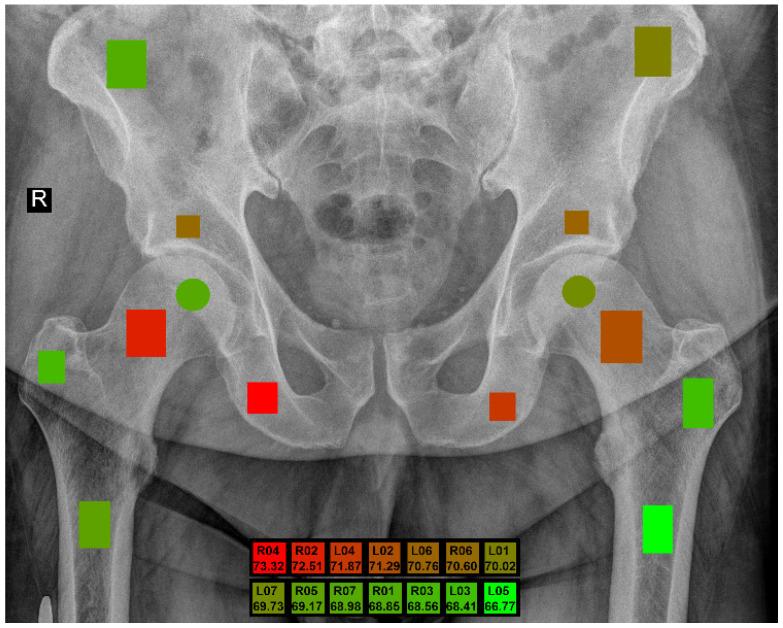

The purpose of this paper is to assess the determination of male and female sex from trabecular bone structures in the pelvic region. The study involved analyzing digital radiographs for 343 patients and identifying fourteen areas of interest based on their medical significance, with seven regions on each side of the body for symmetry. Textural parameters for each region were obtained using various methods, and a thorough investigation of data normalization was conducted. Feature selection approaches were then evaluated to determine a small set of the most representative features, which were input into several classification machine learning models. The findings revealed a sex-dependent correlation in the bone structure observed in X-ray images, with the degree of dependency varying based on the anatomical location. Notably, the femoral neck and ischium regions exhibited distinctive characteristics between sexes. This insight is crucial for medical professionals seeking to estimate sex dependencies from such image data. For these four specific areas, the balanced accuracy exceeded 70%. The results demonstrated symmetry, confirming the genuine dependencies in the trabecular bone structures.

本文的目的是评估从骨盆区域的小梁骨结构确定男性和女性性别的方法。该研究包括分析343名患者的数字射线照片,并根据其医学意义确定14个感兴趣的区域,身体两侧各有7个区域以保持对称。使用各种方法获得每个区域的纹理参数,并对数据归一化进行了深入研究。然后评估特征选择方法以确定一小部分最具代表性的特征,将这些特征输入到几个分类机器学习模型中。研究结果显示,在X射线图像中观察到的骨结构存在性别依赖性相关性,其依赖程度因解剖位置而异。值得注意的是,股骨颈和坐骨区域在两性之间表现出独特的特征。这一见解对于试图从此类图像数据中估计性别依赖性的医学专业人员至关重要。对于这四个特定区域,平衡准确率超过70%。结果显示出对称性,证实了小梁骨结构中存在真正的依赖性。